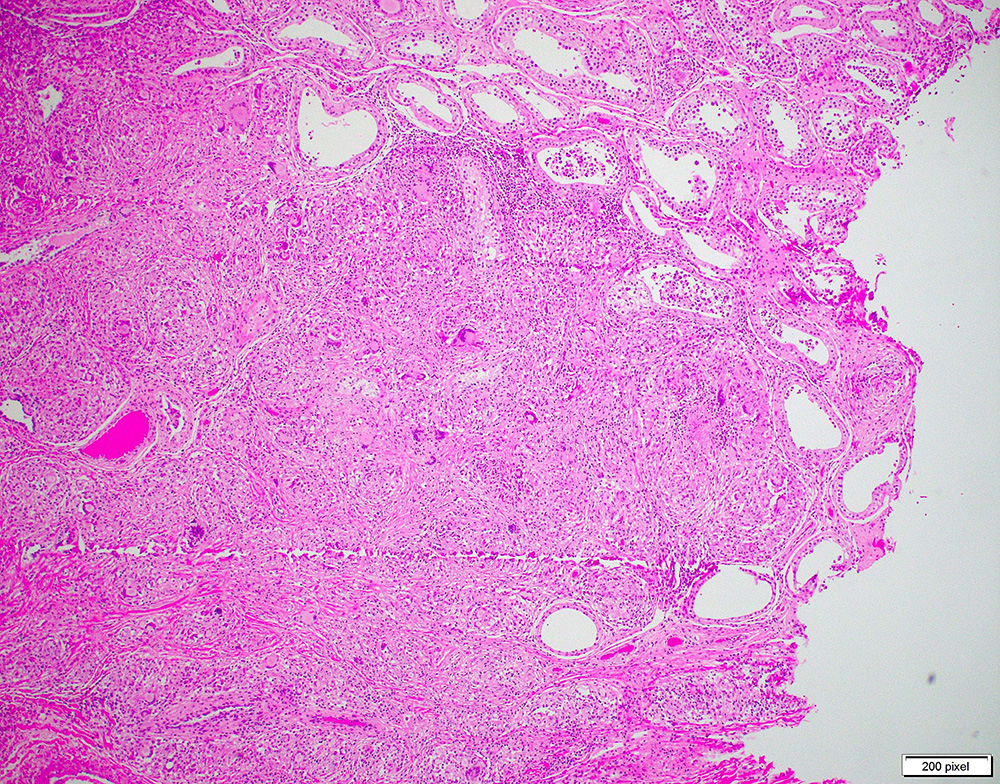

Testicular Mass

A 27-year-old African-American male presented with painful left testicular mass. He noticed a slight fluctuation in the size of the mass over the past four months, as well as subjective fever and chills. He denied dysuria, discharge, and gross hematuria. Initial workup revealed a mildly elevated alpha-fetoprotein (AFP) level (350 U/L) with normal beta-HCG and LDH.

Ultrasound exam revealed a 1.6 cm hypoechoic left testicular mass and a 0.6 cm right testicular mass.

Patient has a past medical history significant for epididymitis status post partial antibiotic treatment complicated by medication noncompliance a year ago. He underwent left radical orchiectomy.